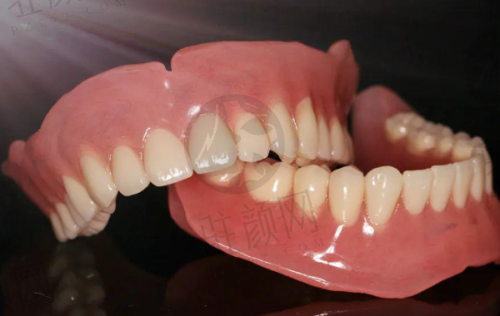

门诊部配备了高端的口腔诊疗设备,引入了智能数字化技术,以确保诊疗的精细性和效率。在种植牙方面,采用数字化微创种植技术,如闺蜜的妈妈做的半口 All - on - 4 种植,医生先用德国 CBCT 拍 3D 口腔片,精细定位神经和血管,再用导板辅助种牙,伤口小,术后当天就能戴临时牙吃饭,3 个月即可修复好。在牙齿矫正方面,拥有“美亚仪 AI 导航口扫仪”,用小探头在嘴里扫一圈,3 分钟就能在电脑上看到矫正后的 3D 成效,还能模拟每个阶段的变化,告别了传统咬石膏模型的方式。